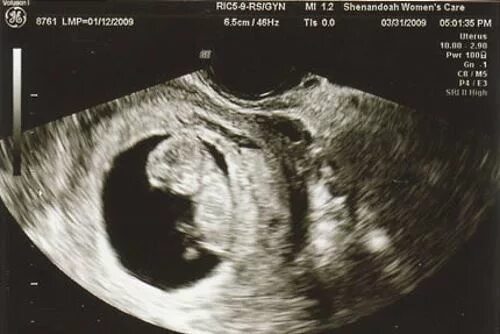

10 недель какие ощущения